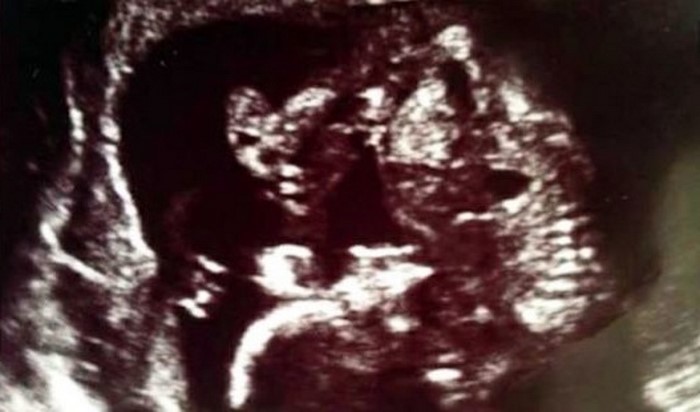

Pero la sorpresa no llegó sola. Después de una de las primeras sesiones de ultrasonido, los doctores les informaron a los futuros padres que estos no esperaban un bebé solo, sino gemelos. ¡Joanna y Steve, locos de alegría, inmediatamente se apresuraron a comprar un segundo conjunto de ropa para bebés!

Sin embargo, Shaniece comenzó a sospechar que, con un par de gemelos, el asunto no se terminaba. El vientre de la madre sustituta, que hasta hace poco no era tan grande, ahora crecía a pasos agigantados. ¡De hecho, una nueva sorpresa resultó ser un verdadero shock para todos!

Al final, a la luz vinieron no dos, sino tres criaturas – dos niñas y un niño. El embarazo transcurrió casi sin problemas, Joanna y Steve le proporcionaron toda la ayuda necesaria a la madre sustituta.